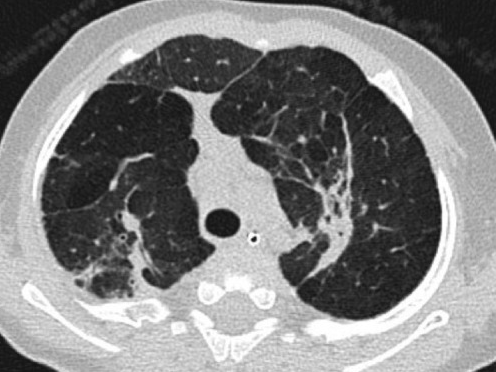

- Zones d’hyperinflation et d’atélectasies

- Epaississement interstitiel (exsudat d’éosinophile)